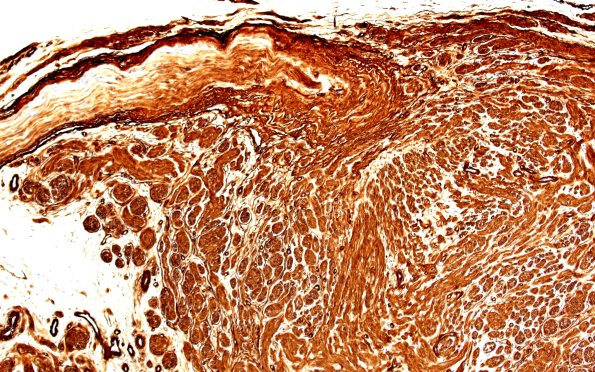

Washington University Experience | PERIPHERAL NEUROPATHY | 19 TRAUMATIC INJURIES | 1C2 Neuroma, traumatic (Case 1) CollIV 10X

1C2-5 Collagen IV stains many elements in the neuroma (perineurium, Schwann cells) as well as the vasculature. (Coll IV IHC)